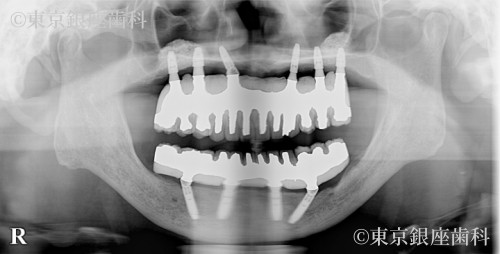

Before

After

疾患 歯牙部分欠損

施術内容 ワンデイインプラント

嘔吐反射で入れ歯が使えず複数医院で治療を断られていたが、当院の精密診断でワンデイインプラントが可能と判明。現在は上下とも安定。

上下ワンデイインプラント(サイナスリフト併用)